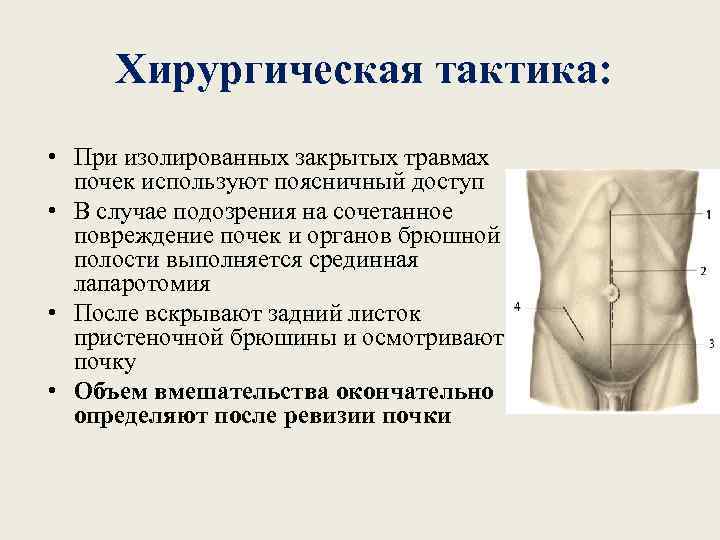

Хирургическая тактика: • При изолированных закрытых травмах почек используют поясничный доступ • В случае подозрения на сочетанное повреждение почек и органов брюшной полости выполняется срединная лапаротомия • После вскрывают задний листок пристеночной брюшины и осмотривают почку • Объем вмешательства окончательно определяют после ревизии почки